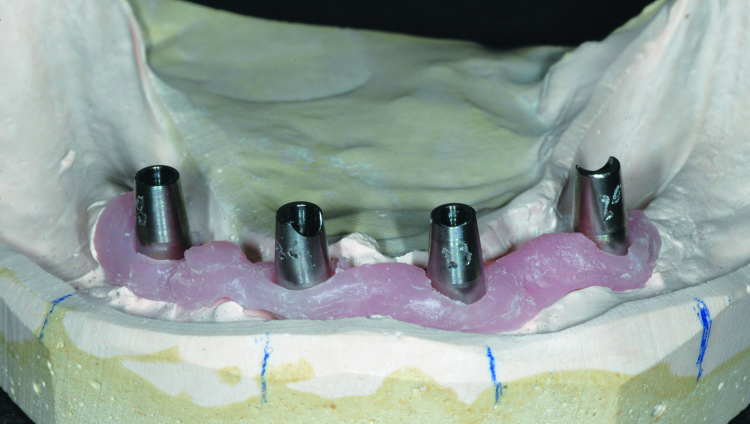

Fig. 3: Duplication of an acceptable denture serves as a custom tray. Holes of sufficient diameter to accommodate impression copings have been prepared.

Fig. 4: Open tray impression copings seated on the dental implants. One implant is selected for disuse and covered with a transmucosal abutment.

Fig. 5: Completed final impression using the custom tray and light body and medium body PVS, as well as rigid bite registration material around the impression copings to eliminate any movement of the copings.

Fig. 6: Completed final impression using the custom tray and light body and medium body PVS, as well as rigid bite registration material around the impression copings to eliminate any movement of the copings.

Because the existing dentures were made within the last five years and were acceptable with regard to tooth position and vertical dimension, it was decided that clear, acrylic resin duplicates of each denture would be made to serve as custom trays.[7] Double-sided impressions of each denture were made and delivered to the dental laboratory for fabrication of the duplicates. Once processed, the copy denture borders were shortened by 2 mm to allow border moulding. The duplicate of the mandibular denture clearly showed the position of each Locator housing and therefore the position of the dental implants. Holes of adequate diameter to allow the duplicate denture to be placed in the patient’s mouth over impression copings were prepared (Fig. 3). The intaglio surface of both the upper and lower duplicate denture were relieved to allow for a wash impression.

The patient returned for final impressions, and the Locator abutments were removed and kept in appropriate order to avoid confusion when reseating them at the appointment completion. Open tray impression copings were connected to each of the four dental implants to be restored and tightened into place; one implant with greater bone loss and placed significantly more shallowly than the rest was omitted (Fig. 4). Light-body polyvinyl siloxane (PVS) was injected around the base of each impression coping and medium-body PVS was placed in the custom tray.

The tray was seated, ensuring that the impression copings were completely accessible through the holes previously prepared. The patient was instructed in facial and tongue movement to achieve proper peripheral border extension. Regisil Rigid (Dentsply Sirona) bite registration material was injected around each impression coping to rigidly adhere them to the impression tray. This step is critical as reliance on flexible impression material may allow transfer error when constructing the working cast.

Once the impression materials were fully set, the screws retaining the impression copings were removed and the final impression and tray were withdrawn from the patient (Figs. 5 & 6). All Locator abutments were reseated and tightened. The final impression of the maxilla was completed with border moulding using modelling plastic and a wash impression with light-body PVS. Upon completion, the patient was dismissed.